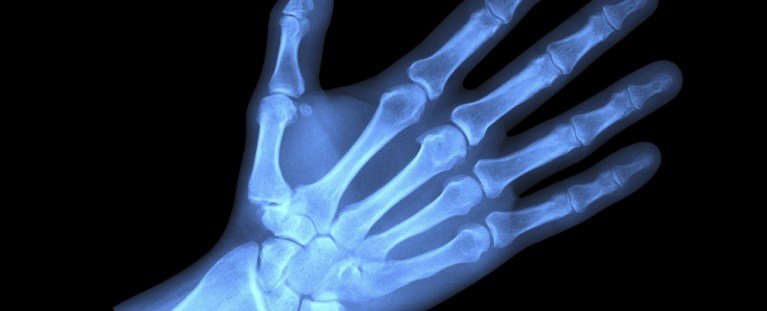

الآن تم العثور على هذه الجسيمات المشتقة من الوقود الأحفوري ، أقل من 5 مم في الحجم ، في عمق عظامنا.

مراجعة جديدة من 62 دراسات يقترح البلاستيك الدقيق والبلاستيك النانوي الأصغر يؤثر على صحتنا الهيكلية بطرق متعددة.

“تشير مجموعة كبيرة من الأبحاث إلى أن البلاستيدات الدقيقة يمكن أن تصل بعمق إلى أنسجة العظام ، مثل نخاع العظام ، وربما تسبب اضطرابات في عملية التمثيل الغذائي ،” يقول علماء الطب رودريغو بوينو دي أوليفيرا من جامعة كامبيناس الحكومية في البرازيل.

بعض من دراسات في البشر ، وجد البشر هذه بقايا البلاستيك المتراكمة في أنسجة العظام عبر الدم ، بعد الابتلاع. هناك، دراسات الحيوانات تظهر أنها يمكن أن تقلل من نمو العظام.

ما هو أكثر من ذلك ، الاضطرابات في العظم – يمكن أن تؤدي الخلايا التي تدعم نمو العظام وإصلاحها – إلى ضعف هياكل العظام ، مما يجعل هذه العظام المعرضة للخطر أكثر عرضة للتشوهات والكسور.